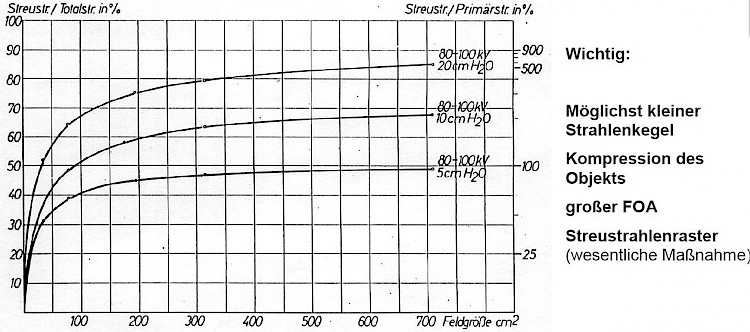

Streustrahlen entstehen überwiegend durch Streuung der Röntgenstrahlen im durchleuchteten Objekt. Die das Bild erzeugende Strahlung ist direkt von der Röntgenröhre auf den Bildträger gerichtet, die Streustrahlung hat jedoch davon abweichende Richtungen. Streustrahlung verursacht eine relativ gleichmäßige Dosisverteilung am Detektor. Der relative Anteil der Streustrahlung steigt stark mit zunehmender Objektdicke und nimmt ab mit höherer Energie der Röntgenstrahlung d. h. steigender Röntgenröhrenspannung.

Je dicker die durchstrahlte Masse und je größer das Bildfeld, desto größer ist der Streustrahlenanteil.

Bei einer Feldgröße von 700 cm² ,d.h. einem Format von 24 cm * 30 cm und einer Objektdicke von 20 cm sind mehr als 80% der auf die Kassette fallende Strahlung, Streustrahlung, d.h. nur etwa 20 % der einfallenden Strahlung tragen zum Bildaufbau bei.

Als weiteres zeigen die Kurven, welchen Einfluss die Größe des eingeblendeten Feldes auf den Streustrahlenanteil hat. Bis zu einer Feldgröße von 200 cm² steigt der Streustrahlenanteil rapide an, danach ist nur noch eine geringe Zunahme zu erkennen.

Die Bildqualität kann man verbessern, indem man das durchstrahlte Volumen möglichst klein hält, z.B. durch Einblendung und oder Kompression. Diese Maßnahme allein reicht nicht aus, um den Anteil an Bild verschlechternder Streustrahlung in erträglichen Grenzen zu halten. Das ist nur mit Hilfe eines Streustrahlenrasters möglich, im folgendem kurz „Raster“ genannt.